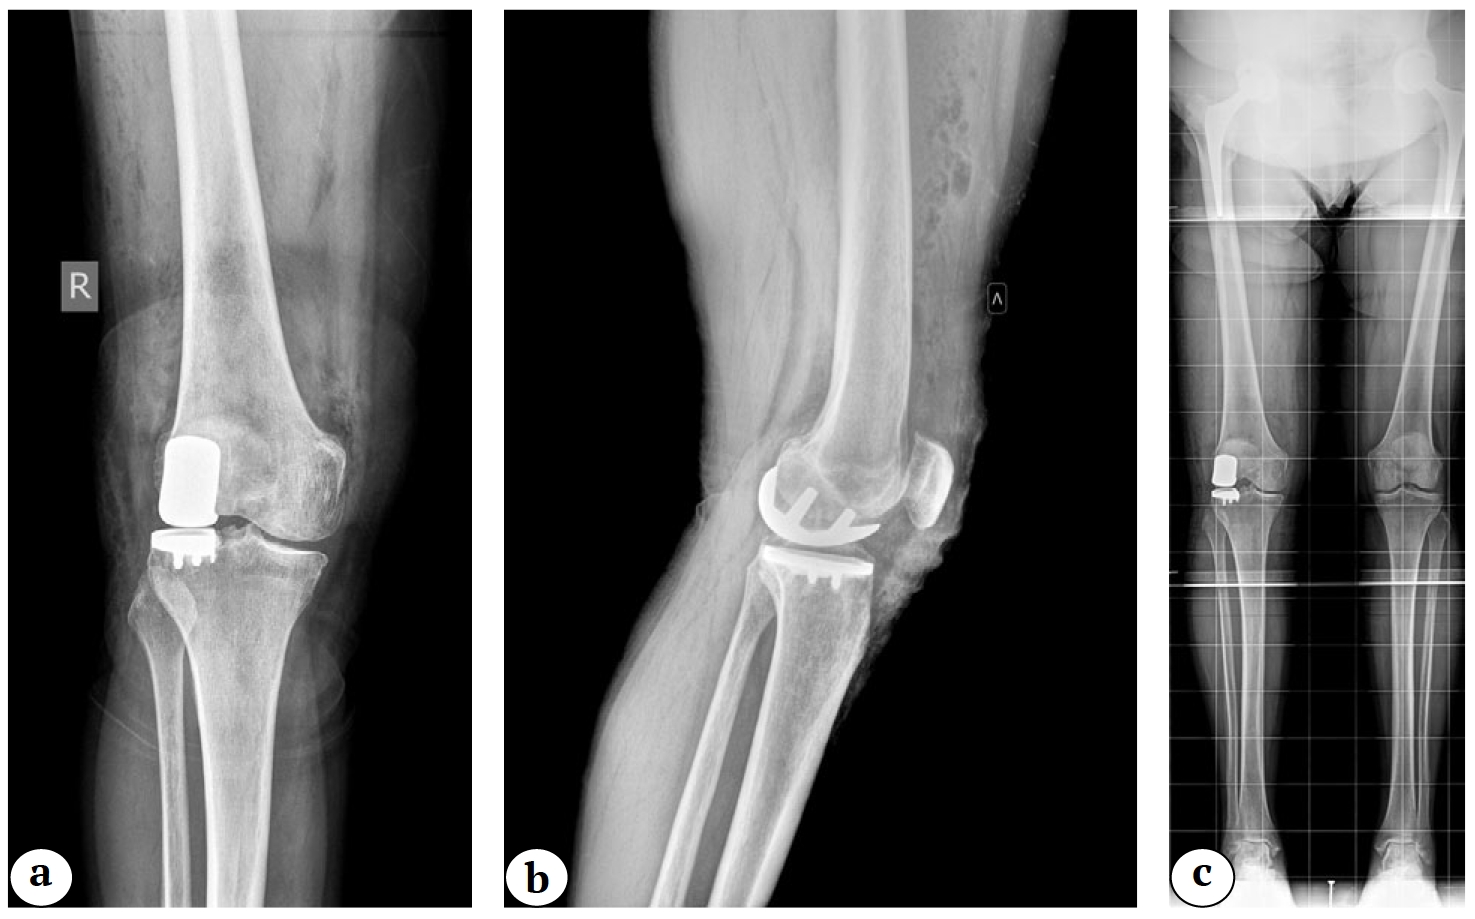

С точки зрения анатомии и биомеханики латеральный отдел коленного сустава значительно отличается от медиального, что делает хирургическую технику его парциального замещения искусственным суставом высокоспецифичной. Анатомические различия медиального и латерального отделов коленного сустава включают ряд важных аспектов: различия в задних наклонах (slope) латерального и медиального мыщелков большеберцовой кости, а также разную величину их переднезаднего размера [3, 4]. Несмотря на то, что костные ориентиры латерального и медиального отделов большеберцовой кости во фронтальной плоскости расположены примерно на одном уровне, за счет хрящевой ткани латеральное плато имеет более выпуклую форму и расположено несколько проксимальнее, чем медиальное плато. Также немаловажно отметить, что латеральный мениск имеет О-образную форму, более подвижен, шире и толще С-образного медиального мениска [5]. Обращая внимание на данную особенность, O.C. Brantigan и A.F. Voshell писали: «Медиальный мыщелок бедренной кости является осью вращения коленного сустава» [6]. Под этим авторы, очевидно, понимали то, что при сгибании медиальный мыщелок бедренной кости, имея выпуклую форму и практически не смещаясь, скользит в углублении медиального мыщелка большеберцовой кости, в то время как латеральные мыщелки бедренной и большеберцовой костей имеют выпуклую форму, в связи с чем смещения наружных мыщелков костей, образующих коленный сустав, друг относительно друга, более значительны. Также важно отметить, что при сгибании медиальный мениск практически недвижим, в то время как латеральный мениск, особенно в крайних углах сгибания, значительно транслируется кзади [7] (рис. 1).

Рис. 1. Различия в мобильности латерального (a) и медиального (b) менисков коленного сустава

Fig. 1. Differences in mobility of the lateral (a) and medial (b) menisci

Рис. 18. Рентгенограммы после выполненного одномыщелкового эндопротезирования латерального отдела коленного сустава в прямой (а) и боковой (b) проекциях; телерентгенограмма (c)

Fig. 18. X-ray images after performing lateral unicompartmental knee arthroplasty in anterior-posterior (a) and lateral (b) projections; full-length X-ray (c)